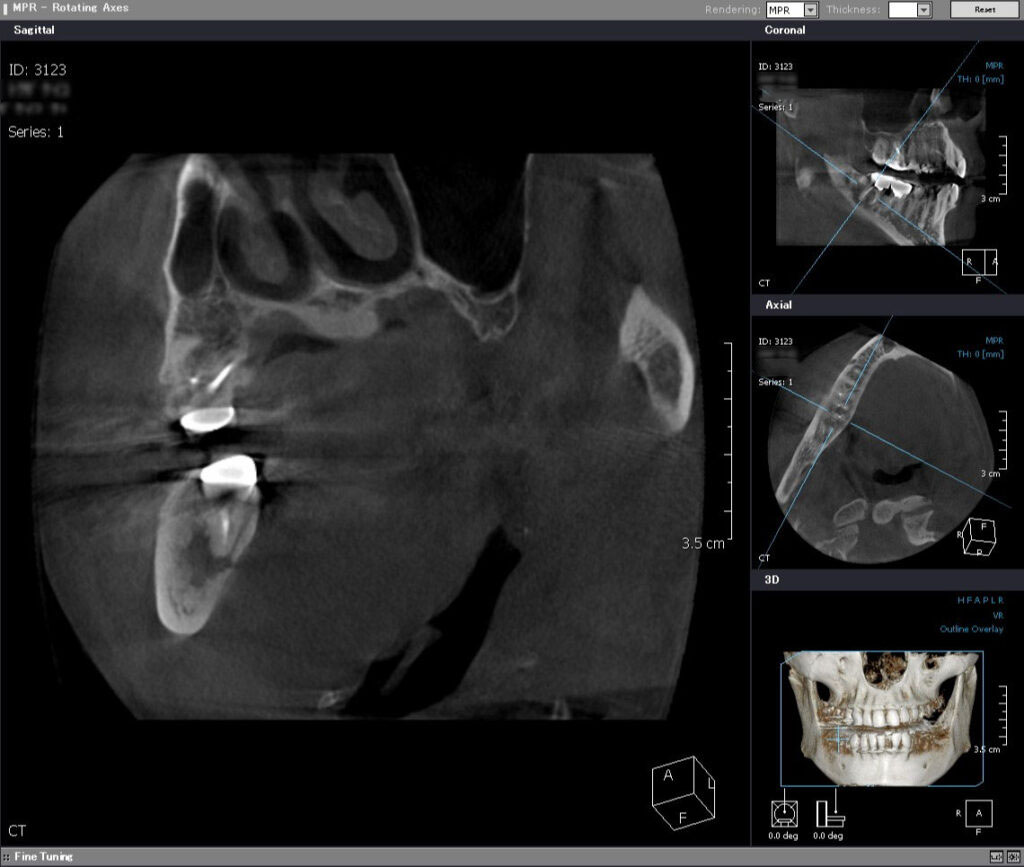

術前CT矢状断

近遠心的(手間から奥に向かって)に、根っこの先に化膿による大きな鶏卵状の境界明瞭な黒い骨透過像を認める。ここまで大きいと一般的には抜歯が適応と言える。

根っこの先の黒い骨透過像(吸収像)をはっきりと認め、下顎の神経束(丸い玉状の像)ギリギリまで拡がっていることがわかる。このままにしていれば、顎の痺れが出現すると考えらえる。